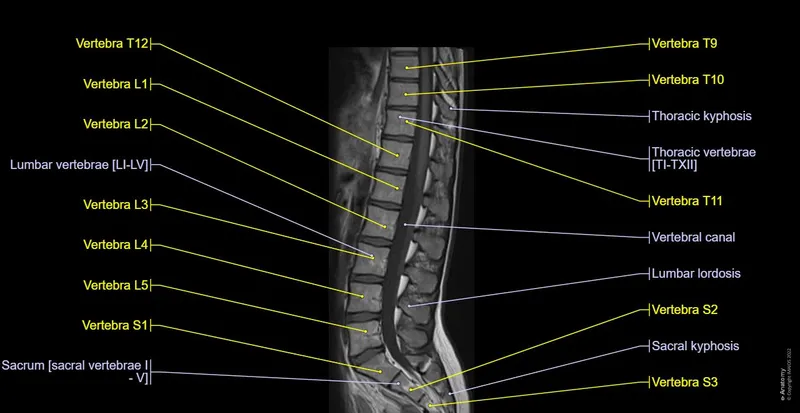

- Spine MRI: Core Assessment

- Vertebral Bodies: Check alignment and height.

- Intervertebral Discs: Evaluate hydration (T2 bright signal) and identify herniation types (bulge, protrusion, extrusion, sequestration).

- Spinal Cord: Assess signal intensity and morphology.

- Neural Elements: Examine nerve roots and facet joints.

⭐ On T2-weighted images of the spine, normal intervertebral discs appear bright due to high water content; dessicated or degenerated discs lose this hyperintensity.